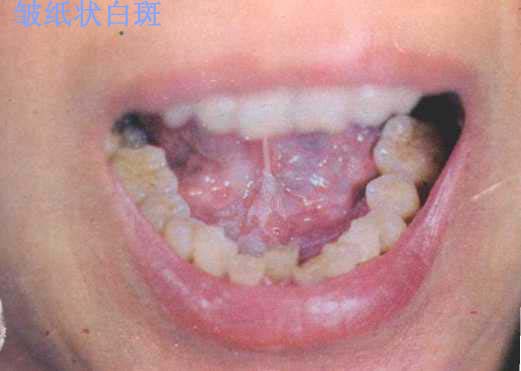

口腔黏膜白斑